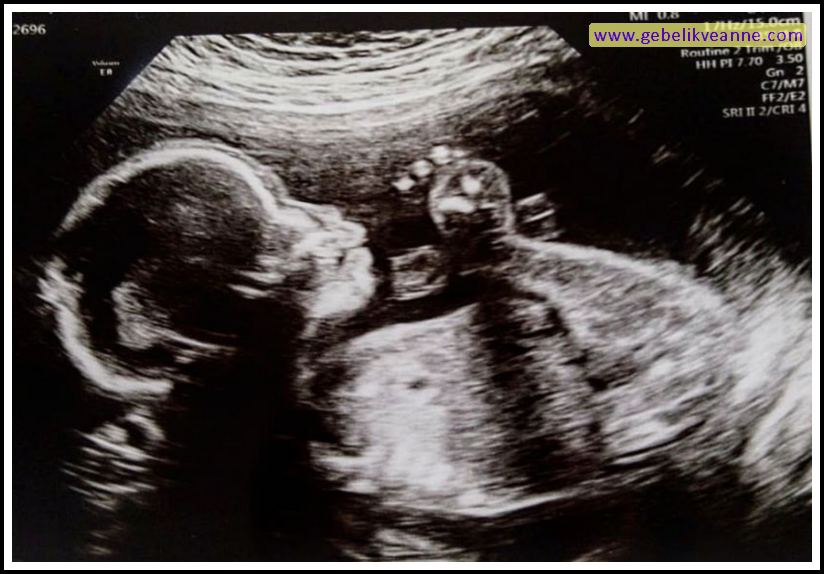

20 Haftalık Gebelik (Hamilelik) ultrason görüntüsü

| 20 haftalık gebelik ultrason görüntüsü |

| 20 haftalık gebelik ultrason görüntüsü 4 boyutlu |

| 20 haftalık gebelik ultrason görüntüsü 3 boyutlu |